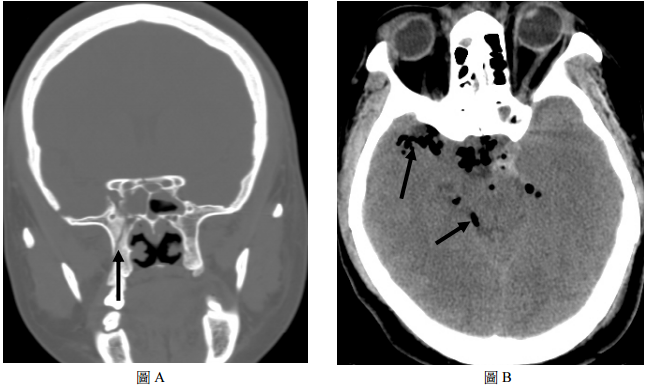

72 17 歲男性,頭部外傷,緊急做的 CT 影像發現顱底有一骨折(如圖 A 箭頭所指處),則在圖 B,箭 頭所指的是顱內:

(A) CSF leakage (B) Traumatic pneumocephalus (C) Fat embolism (D) Traumatic subarachnoid hemorrhage(SAH)